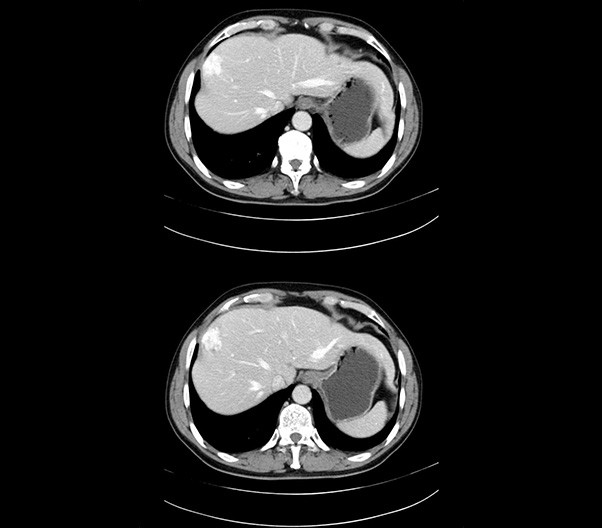

The 1024-pixel image matrix brings superior image clarity (0.6 mm slice thickness) and stimulates the early detection of small lesions, thus improving diagnostic reliance.

臨床畫廊